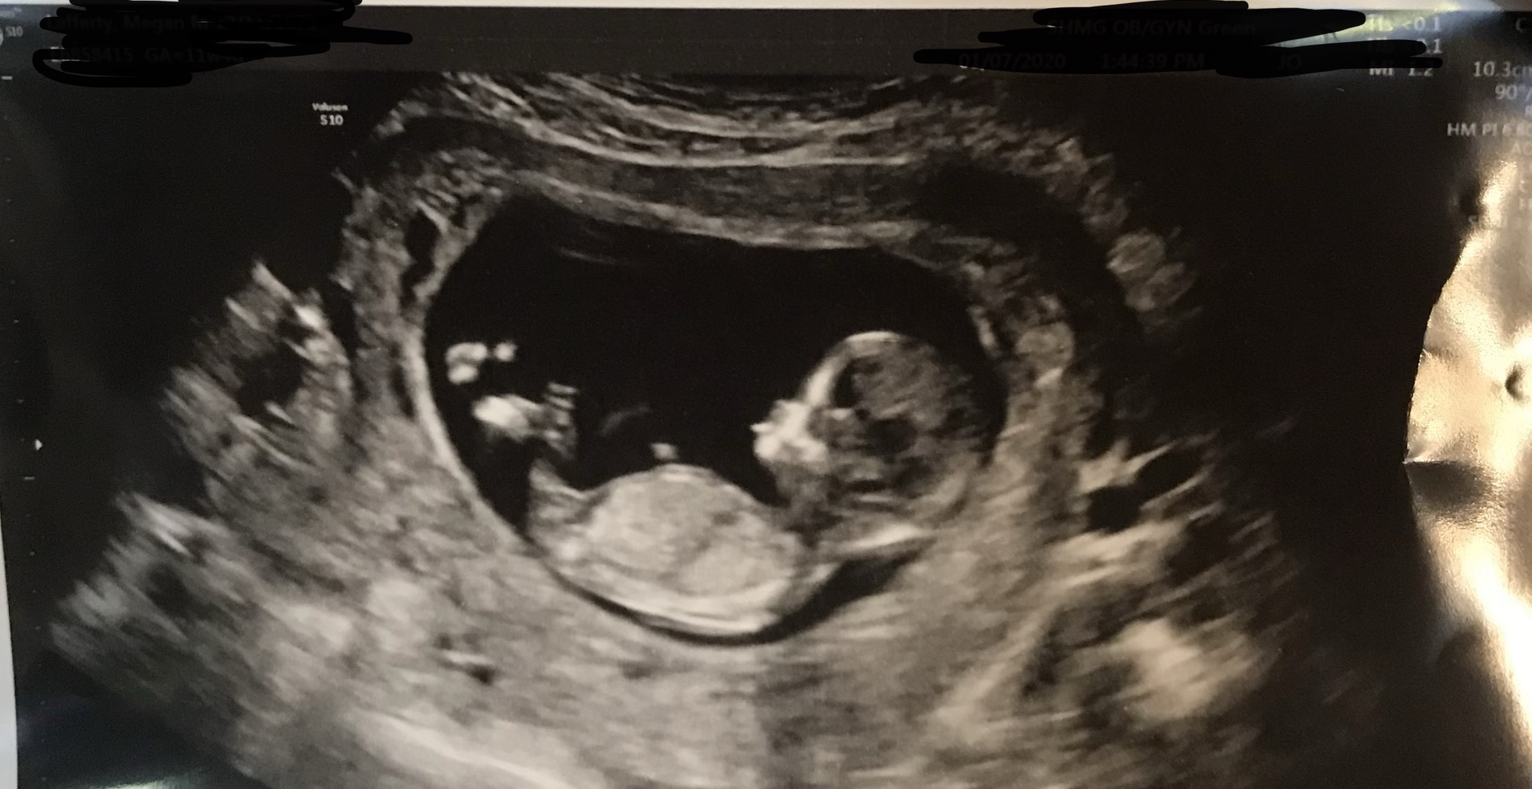

Hi! Please take a look and let us know what you think we are having! Have 3 boys already, hoping for a girl this time. Quite exciting whoever we get!Attachment 42288

It's too early, while the nub is very flat, nubs can still rise and often do.

Thank you for replying. Yeah, digging around a bit more, and found this gestation week range is too early. Still fun to guess as of all the science thats out there, this one seems to hold a bit more merit.